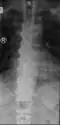

Confluent ossification of multiple contiguous vertebral bodies in diffuse idiopathic skeletal hyperostosis (DISH) -

"Melted candle wax" appearance of calcification and ossification in diffuse idiopathic skeletal hyperostosis (DISH). Note the preponderance on the patient's left side (right side of image). -